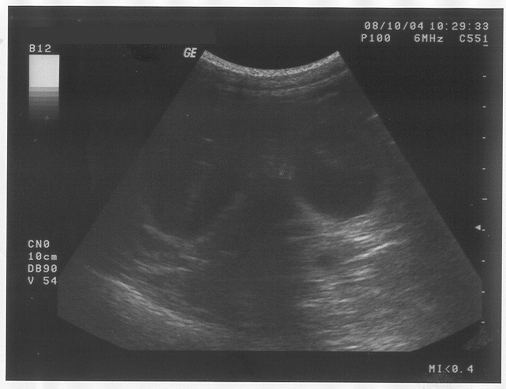

Er hat mir noch mal diesen Glibberkram auf den Bauch geschmiert und dann haben alle ganz fasziniert auf eine Art Fernseher geschaut. Da kam aber weder "Herrchen gesucht" noch Werbung. Eigentlich hab ich da gar nichts erkennen können.

Nur der Mann und Frauchen und Brigitte, die haben sich gefreut und gemeint, dass es wohl wieder mindestens 6 Babies geben wird. Vielleicht sogar mehr. Ich hab euch die Bilder mal mitgebracht - vielleicht könnt ihr ja was entdecken. Für mich sieht das eher aus wie Seifenblasen.